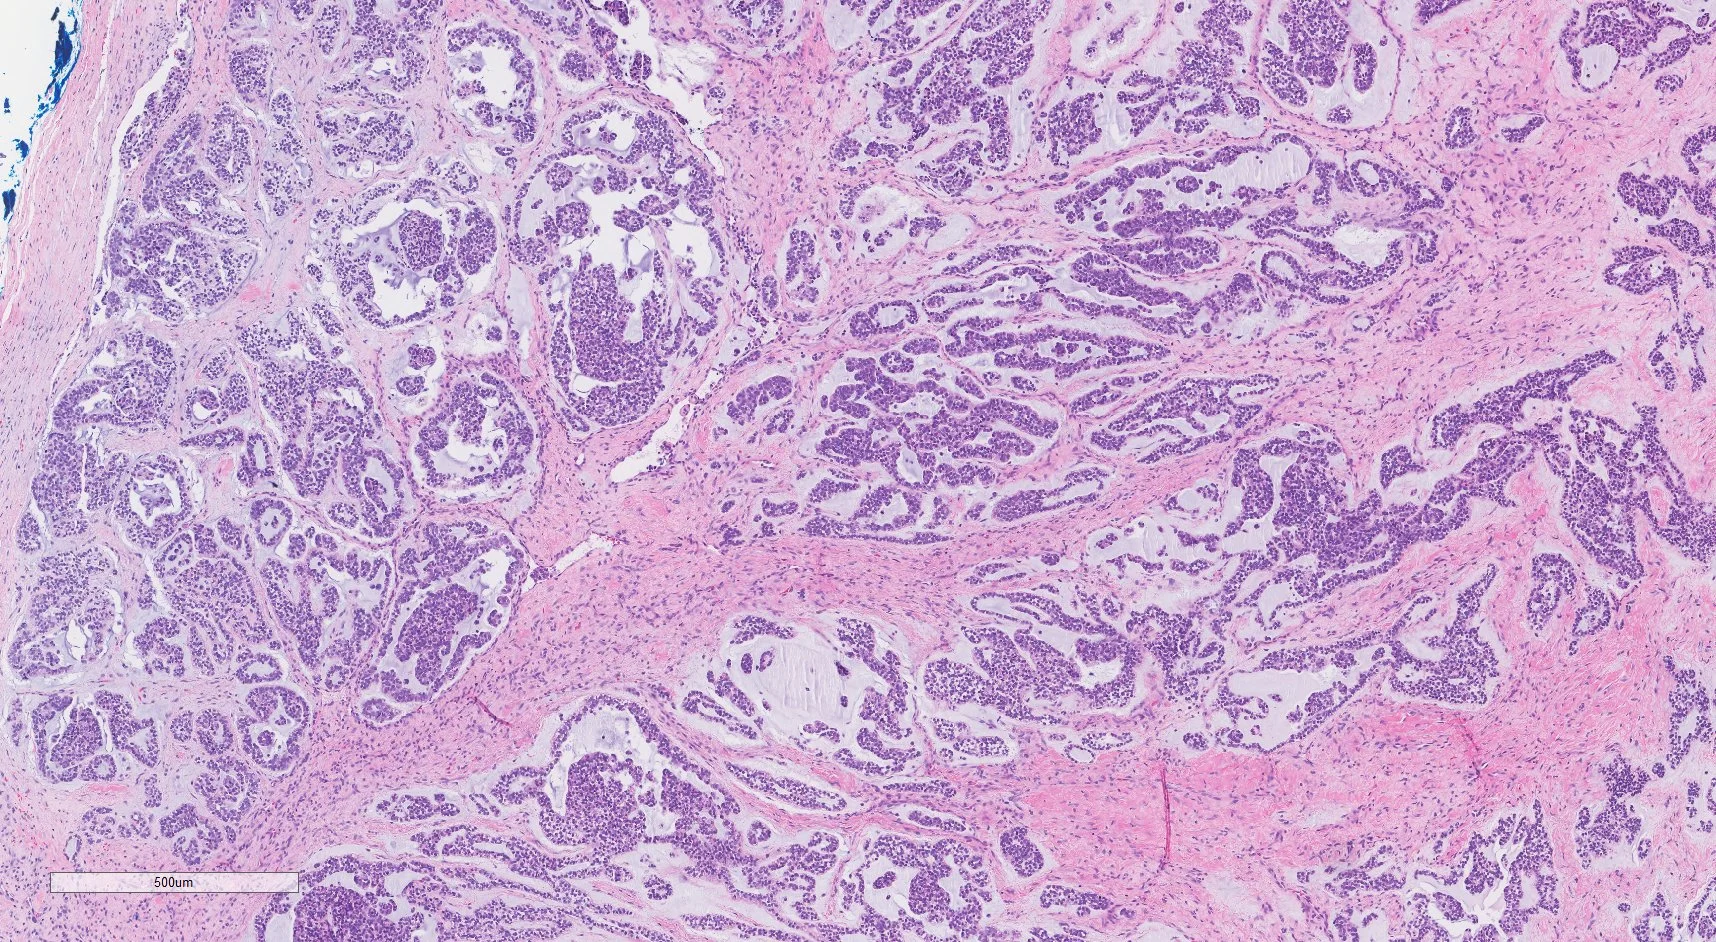

MEC gets its name from how the cells that make up this tumor look under the microscope. Like all tumors with a myoepithelial component, MEC tumors exhibit a wide morphologic and cytologic diversity that is based on four major types of cells, similar to those seen in benign myoepithelioma: spindle, plasmacytoid (hyaline), epithelioid, and clear cell types.

Biopsy: Your doctor will do a biopsy, taking a small sample from the tumor with a needle, to check if the tumor is MEC. They may also do an excisional biopsy, where the entire tumor is removed. An expert, called a pathologist, will study cells from the sample under the microscope and run other tests to see if the tissue is cancer. They will also look for certain changes in chromosomes to confirm that your cancer is MEC.